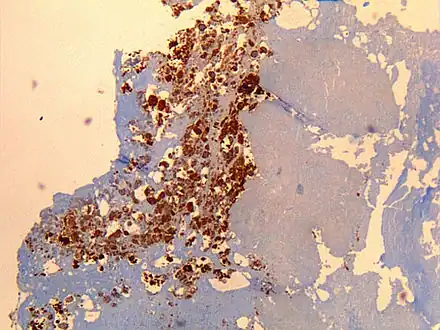

| Immunohistochemistry showing C. burnetii in a heart valve of a 60-year-old with Q fever endocarditis: Monoclonal antibodies and hematoxylin were used for staining; original magnification is ×50. | |